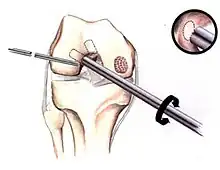

Intact lesions

If non-surgical measures are unsuccessful, drilling may be considered to stimulate healing of the subchondral bone. Arthroscopic drilling may be performed by using an antegrade (from the front) approach from the joint space through the articular cartilage, or by using a retrograde (from behind) approach through the bone outside of the joint to avoid penetration of the articular cartilage. This has proven successful with positive results at one-year follow-up with antegrade drilling in nine out of eleven teenagers with the juvenile form of OCD,[53] and in 18 of 20 skeletally immature people (follow-up of five years) who had failed prior conservative programs.[54]

Hinged lesions

Pins and screws can be used to secure flap (sometimes referred to as hinged) lesions.[55] Bone pegs, metallic pins and screws, and other bioresorbable screws may be used to secure these types of lesions.[56]